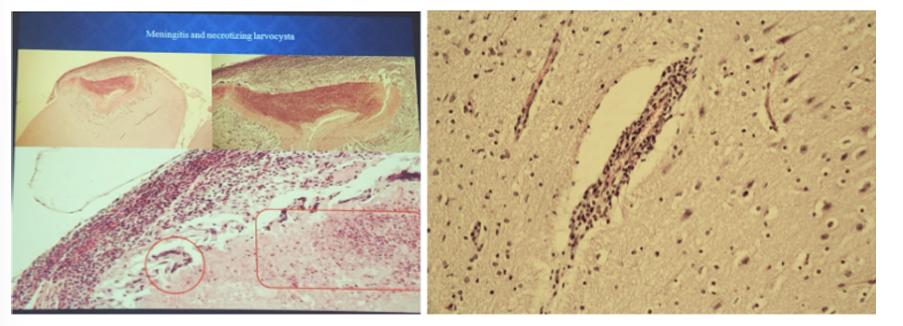

this is?

cysticercus ovis (Mozog/brain)

at periphery of section under the meninges, there is a cysts that intrudes into the brain.